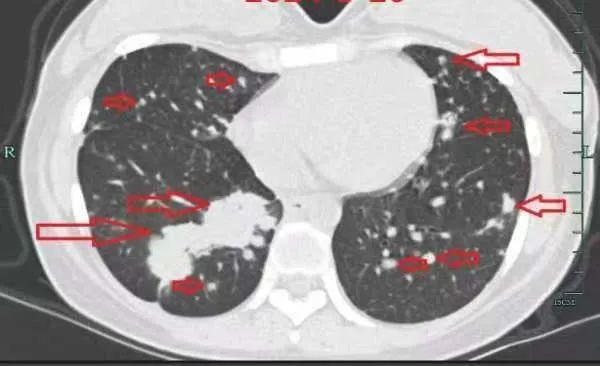

治疗前

入院后,小谢完善了抽血化验及肺部CT、肝脏磁共振等检查,但结果却极其凶险,肺部转移灶如“满天星”,肝脏肿块压迫胆管导致胆红素水平飙升,整个人都“黄”得一塌糊涂。

面对如此棘手的情况,丁主任团队进行了全面且细致的评估,为了有效控制病情进一步恶化,当务之急是立刻开始进行化疗。

在丁主任团队的精心治疗下,小谢开始了化疗。虽然在化疗的过程中经历了副作用,但顶着光秃秃脑袋的小谢依然保持着乐观。